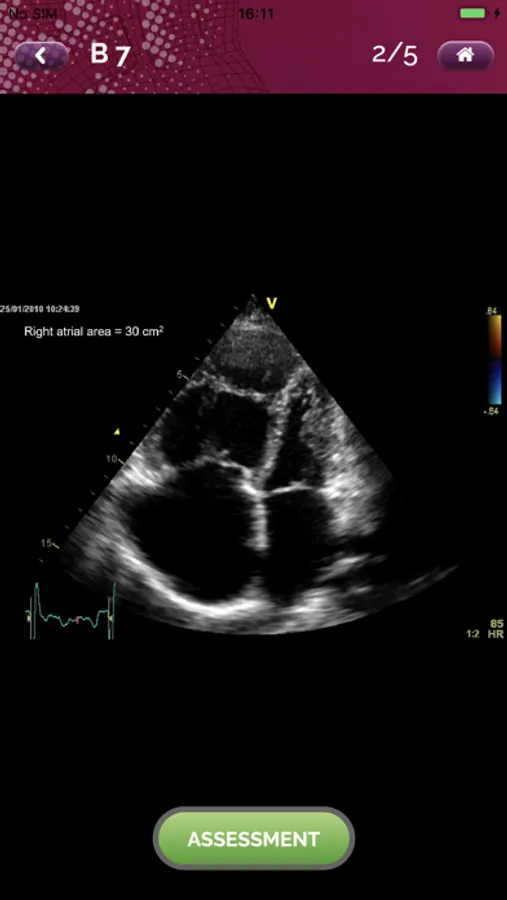

EchoRight Pro Screenshots